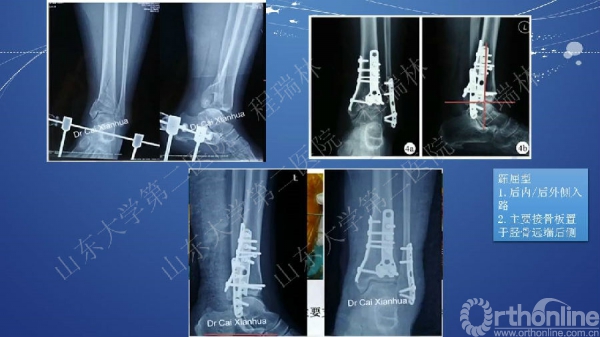

Pilon骨折的手术基本原则

Pilon骨折是踝部的复杂骨折,以高能量损伤、不稳定、软组织损伤严重为特点。手术复杂,并发症常见且严重。一旦治疗失败,常常带来灾难性的后果,如截肢、严重创伤性关节炎后期再关节融合等。

Pilon骨折的治疗目的:软组织保护,恢复下肢力线,解剖复位关节面。